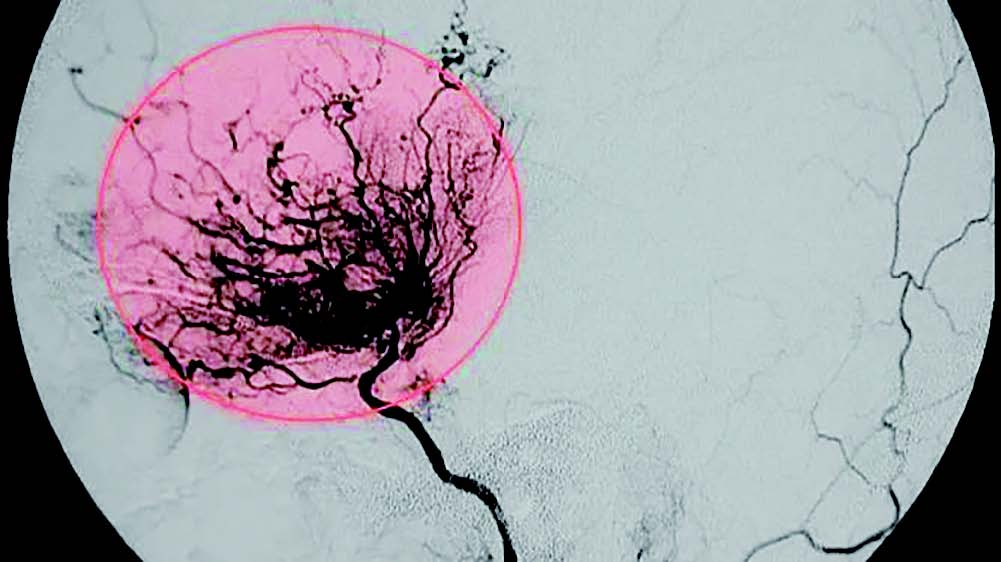

烟雾病是一种病因不明,以双侧颈内动脉末端及大脑前动脉、大脑中动脉起始部慢性进行性狭窄或闭塞为特征,并继发颅底异常血管网形成的脑血管病。由于这种颅底异常血管网在脑血管造影图像中形似烟雾,故称为烟雾病。